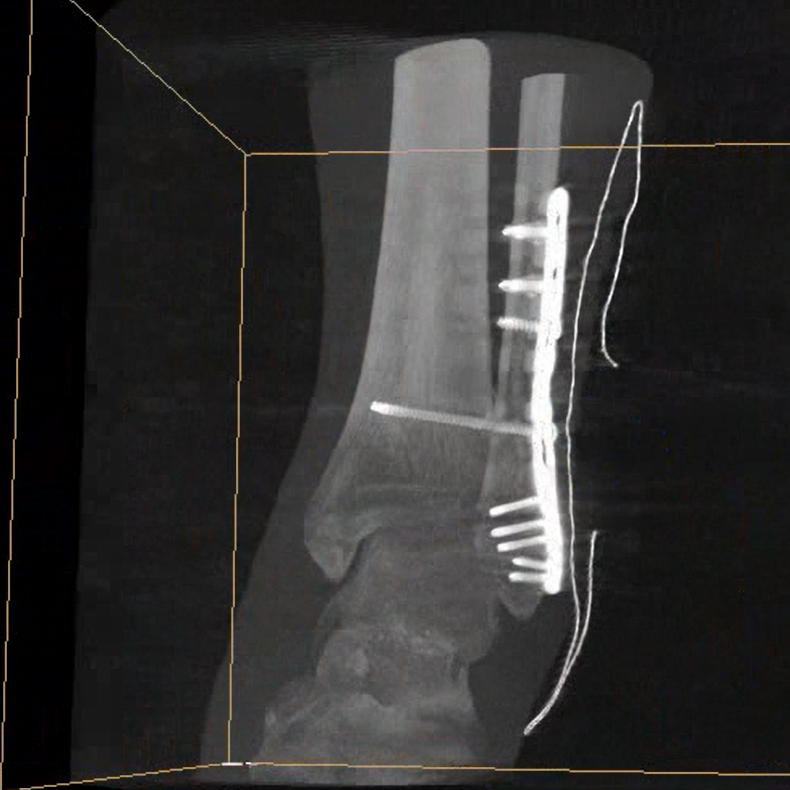

術(shù)中三維成像和橫斷面圖像提供多角度的手術(shù)診斷信息,輔助醫(yī)生進(jìn)行術(shù)中評(píng)估判斷,諸如骨折復(fù)位情況和內(nèi)植入螺釘?shù)某叽绾臀恢?,輔助手術(shù)更好地完成。